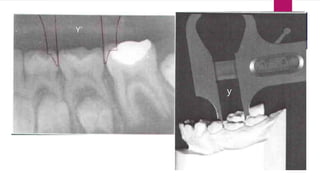

Radiographic Method

[HUCKABA’S]

 Dental cast and patient radiograph is required

 Radiograph may be periapical or OPG

 Reaquired Mesiodistal width of each tooth is measured separately

on the cast and radiograph.

 Calculate with formula x = x’y/y’

 X is unerupted tooth permanent

 Y is erupted tooth on cast deciduous

 X’ is unerupted tooth on radiograph permanent

 Y’ is erupted deciduous tooth on radiograph

POINTS TO BE NOTED

 BAR means something on the radiograph

 We take Y’ to check the magnification

 The formula given above is used to cancel the magnification in order to

get the actual value.

Y’

y